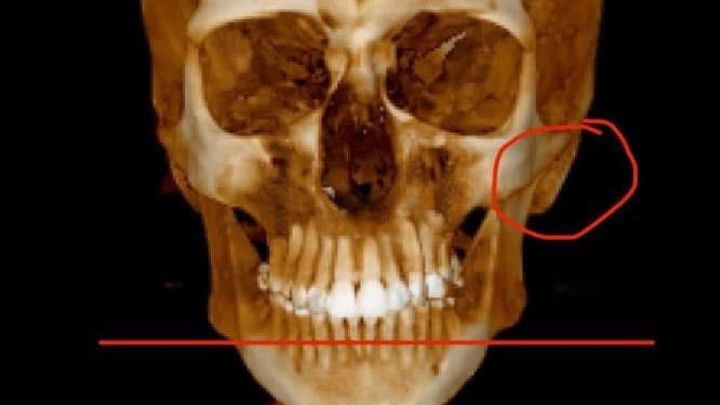

I was diagnosed with TMJ this year, which is a whole new adventure that I’m struggling to begin since no oral surgeon wants to see someone with Ehlers-Danlos Syndrome since it is a connective tissue disorder. TMJ is very common with EDS. My only choice right now is to travel down to NYC again to see an oral surgeon knowledgeable in EDS, but that will all be out of pocket expenses.

My cervical spine curves the opposite way (kyphosis).